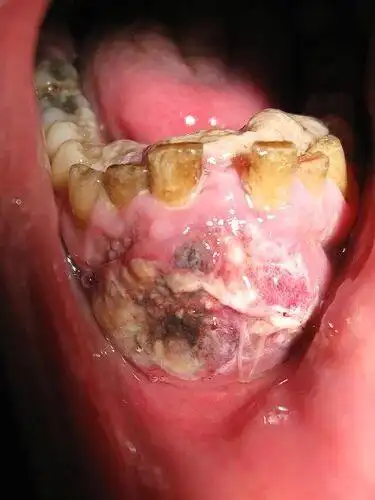

口腔溃疡90%会恶化成口腔癌,这是真的吗?

口腔癌

口腔溃疡的尽头,可能是口腔癌_手机搜狐网